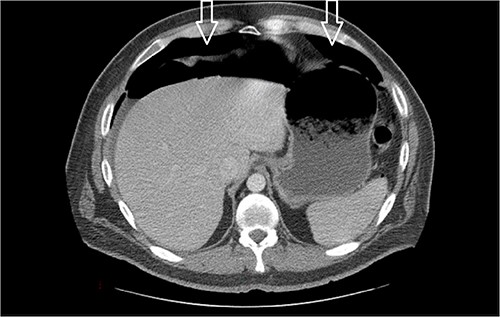

Ten days prior to ER admission, he presented to an outlying hospital with nausea, vomiting and diarrhea episodes and underwent a LC. A baseline computerized tomography scan (CT) demonstrated pneumoperitoneum (see Fig. 1). Because of the lack of inflammatory changes in the GI tract, viscus perforation was an unlikely consideration. An EL was performed that came back negative and he was subsequently discharged.